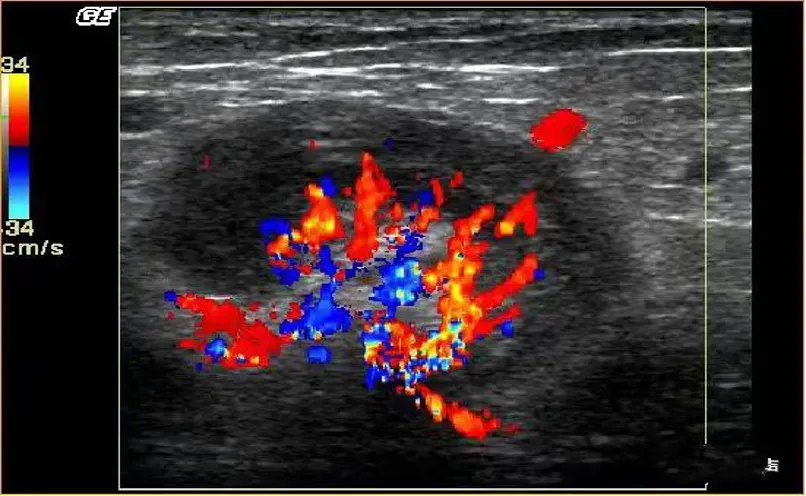

淋巴瘤

● 淋巴结不同程度肿大,多发,呈椭圆形、圆形,纵横比<2。

● 被膜清晰或不清晰,淋巴结之间可见融合。

● 皮质明显增厚呈低回声,不均匀,无液化、钙化;特征性回声改变为淋巴结内回声近似无回声的极低回声。

● 髓质变形或显示不清,或消失。

● 淋巴结内血流信号轻度或明显增多,分布杂乱;典型血流改变为淋巴结内血流信号丰富,红、蓝色血流信号充满整个淋巴结。

● 动脉血流速度加快,阻力指数正常或偏高。

淋巴瘤的血流信号在所有淋巴结中最为丰富。

淋巴结的内部回声一般表现为较均匀的低回声,当发生坏死时,其内部回声可相当低,接近无回声。